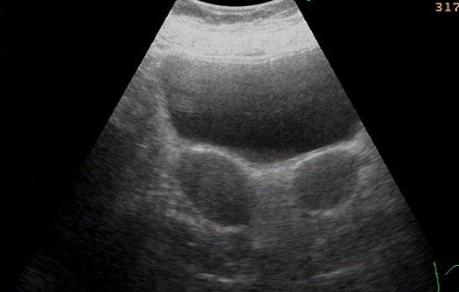

双子宫是指子宫两侧副中肾管在胚胎分裂发育的时候没有融合完全,导致其各自发育形成两个子宫和两个宫颈,双子宫的病例很少,一般是在人工流产,产检的时候偶然发现,双子宫畸形的症状一般有哪些症状呢?

两侧副中肾管完全未融合,各自发育形成两个子宫和两个宫颈,阴道也完全分开,左右侧子宫各有单一的输卵管和卵巢。